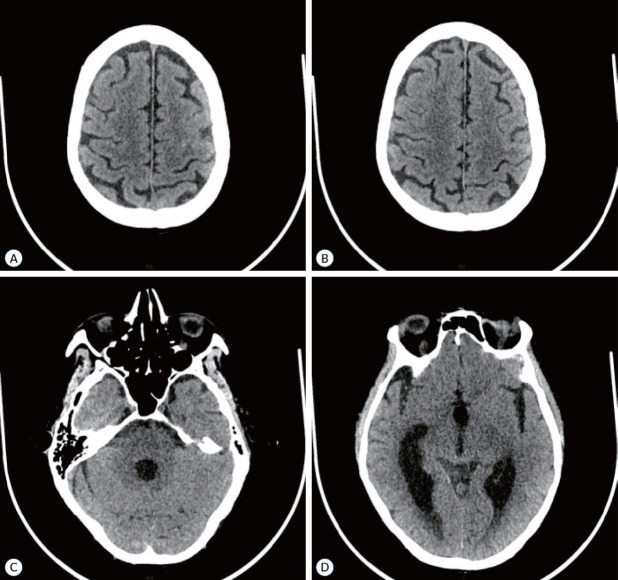

Microscopic polyangiitis (MPA) is a rare autoimmune disorder characterized by small-vessel vasculitis and the presence of anti-neutrophil cytoplasmic antibody (ANCA). Typically, MPA primarily affects the respiratory system, kidneys, and skin, with infrequent involvement of the nervous system, resulting in neuropathy. However, the occurrence of subarachnoid hemorrhage (SAH) in MPA is exceedingly rare, especially when it is accompanied by hemorrhagic events in multiple organs. This case report details the clinical presentation of a 61-yearold male patient diagnosed with MPA who experienced an exceptionally uncommon occurrence of SAH, coupled with extensive bleeding manifestations including epistaxis, skin purpura, and gastrointestinal bleeding. Notably, the patient's symptoms exhibited potential improvement following a treatment regimen consisting of rituximab and glucocorticoids. This case emphasizes the critical importance of promptly recognizing and comprehensively managing rare complications in MPA patients to optimize clinical outcomes.

Abstract Image